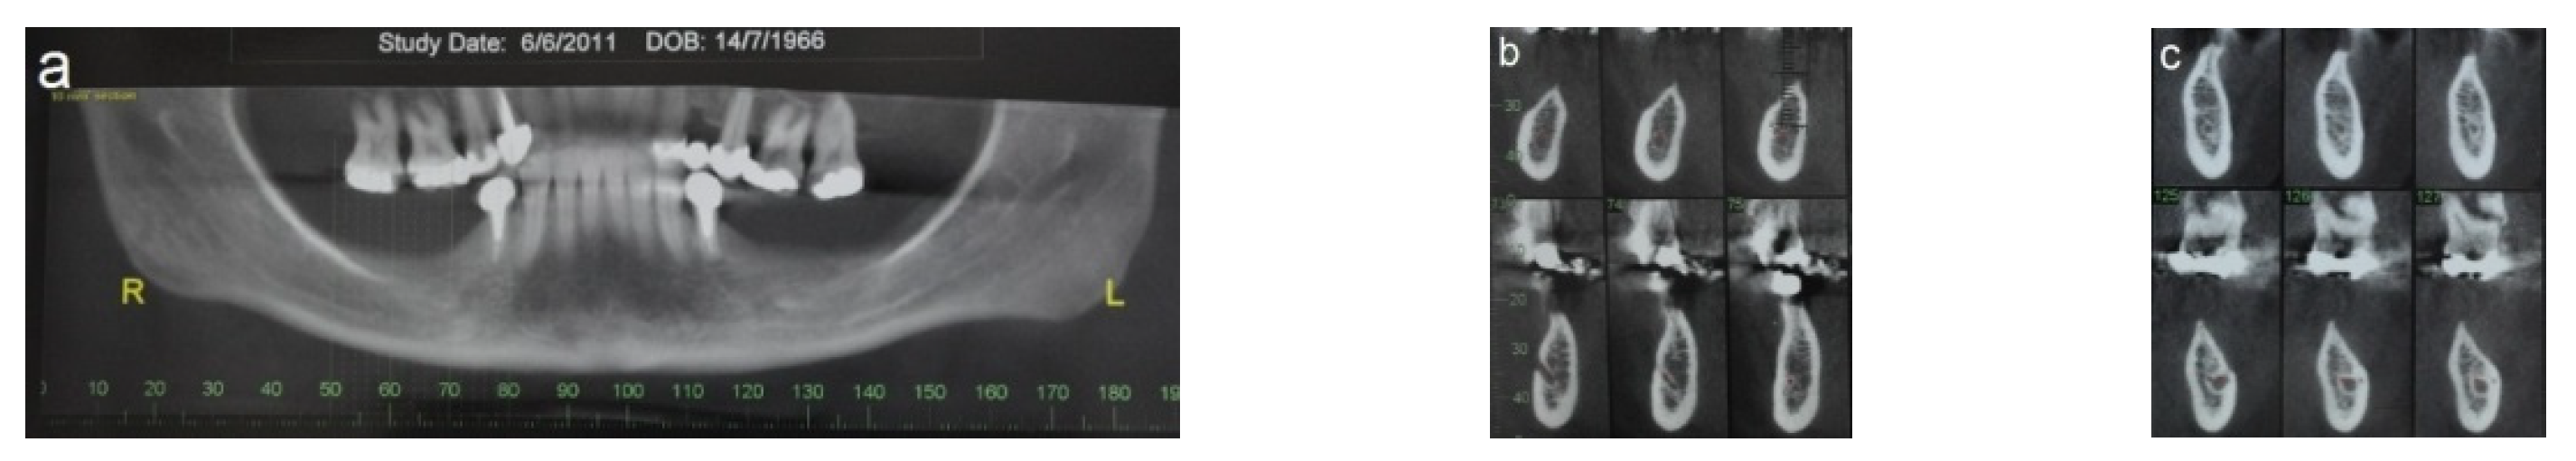

2.5.2. Case 2 (Patient No. 12)

A 47-year-old healthy female patient was referred to our clinic for bilateral augmentation of the posterior mandible and dental implant placement. She was treated using the honeycomb technique and underwent bilateral augmentation of the posterior mandibular ridges. Figure 7 presents the CBCT scans before and after the augmentation procedure (Figure 7a–f), as well as the stable outcomes observed after 13 years of follow-up (Figure 7g,h).

Figure 7.

(a–c) CBCT scan images reveal severe horizontal atrophy in the molar regions bilaterally. (d–f) CBCT scan images taken after honeycomb bone grafting demonstrate significant bone gain. (g); Implants, (h,i) images taken 13-year follow-up after implant loading.